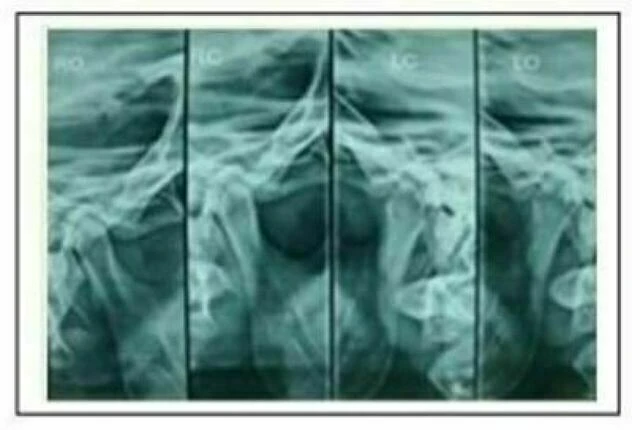

d. Tomogram: Cho các trường hợp có dấu hiệu bất thường về khớp thái dương hàm rõ rệt, cần phải có thêm phim này trong bệnh án.